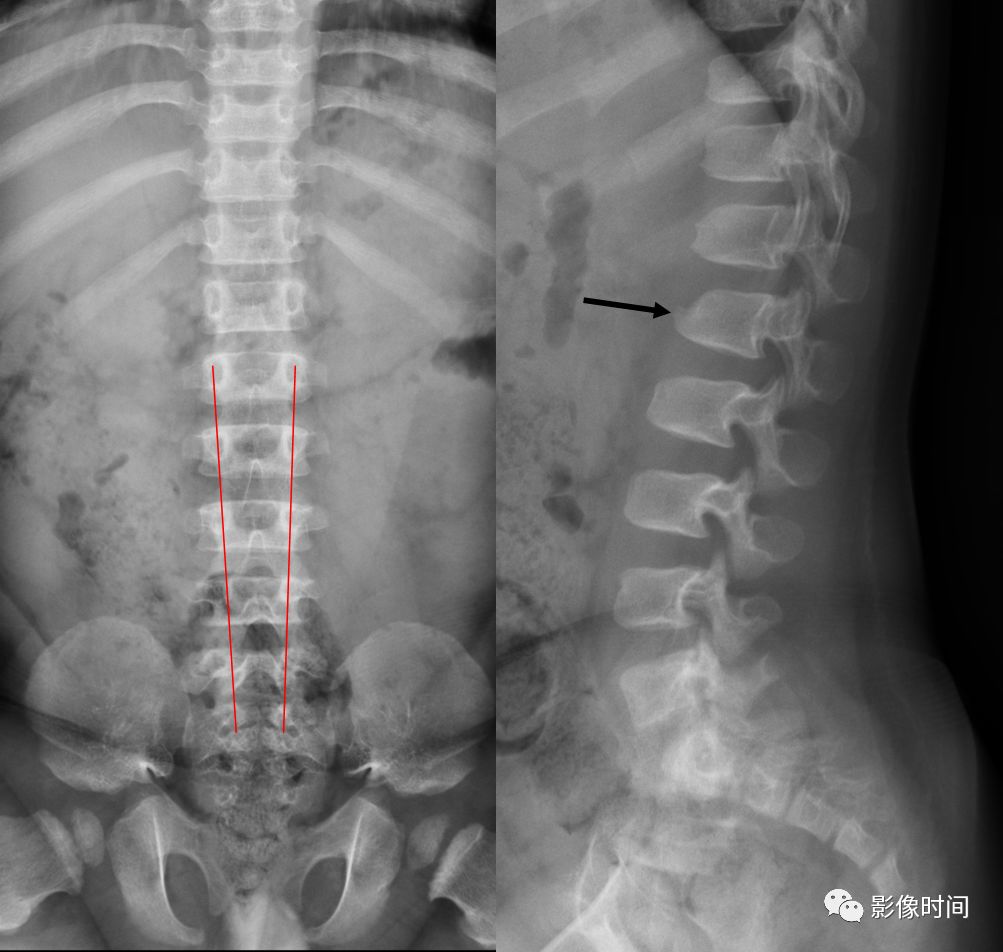

图. 男性,14岁,X线下典型的椎体扇贝样改变

图. 男性,7岁,NF1伴脊柱侧凸;X线示腰椎侧凸畸形(a), CT示椎体及椎板椎弓根破坏,椎管扩大(b、c);MRI示椎管扩张,椎旁肿瘤(c、d);CT横断面示椎弓根发育不良,椎体边缘破坏(e)

病例 2,2 岁男孩,软骨发育不全。腰椎侧位片可见椎体呈子弹形(黑箭),另外还可以见到椎体后缘扇贝样凹陷,正位片课件典型的腰椎弓根间距逐渐缩小(红线)。